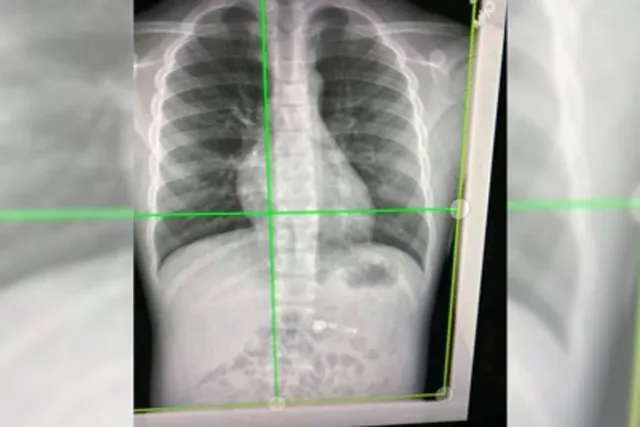

London: Using high-energy X-rays, scientists have found how Covid-19 damages even the smallest blood vessels in human lungs.

Scientists from University College London and the European Synchrotron Research Facility (ESRF) used a new revolutionary imaging technology called Hierarchical Phase-Contrast Tomography (HiP-CT), to scan donated human organs, including lungs from a Covid-19 donor.

Using HiP-CT, the research team saw how severe Covid-19 infection 'shunts' blood between the two separate systems -- the capillaries which oxygenate the blood and those which feed the lung tissue itself.

Such cross-linking stops the patient's blood from being properly oxygenated, which was previously hypothesised but not proven, said the team in the paper published in the journal Nature Methods.

The HiP-CT technique provides the brightest source of X-rays in the world at 100 billion times brighter than a hospital X-ray.

Due to this intense brilliance, researchers can view blood vessels five microns in diametre (a tenth of the diametre of a hair) in an intact human lung, whereas a clinical CT scan only resolves blood vessels that are about 100 times larger, around 1mm in diametre.